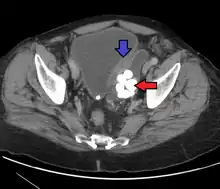

Colonic diverticulum Diverticulum of the urinary bladder of a 59-year-old man, transverse plane

Diverticulum of the urinary bladder of a 59-year-old man, transverse plane Bladder diverticula containing stones: the bladder wall is thickened due to possible transitional cell carcinoma.

Bladder diverticula containing stones: the bladder wall is thickened due to possible transitional cell carcinoma.- Bladder diverticula as seen on ultrasound with doppler[18]